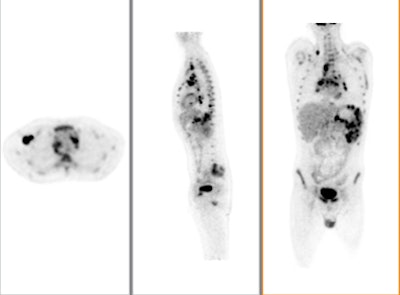

![]() |

| Above, PET and PET/CT fused data post-therapy for lymphoma. Below, PET and PET/CT fused data pretherapy for lymphoma. The images illustrate a patient's lymphoma staging to assess initial treatment strategy and follow-up study after initial treatment to plan subsequent treatment. The images were taken by Philips Healthcare's Gemini TF with time-of-flight. Images courtesy of Philips and University Hospitals Case Medical Center in Cleveland. |